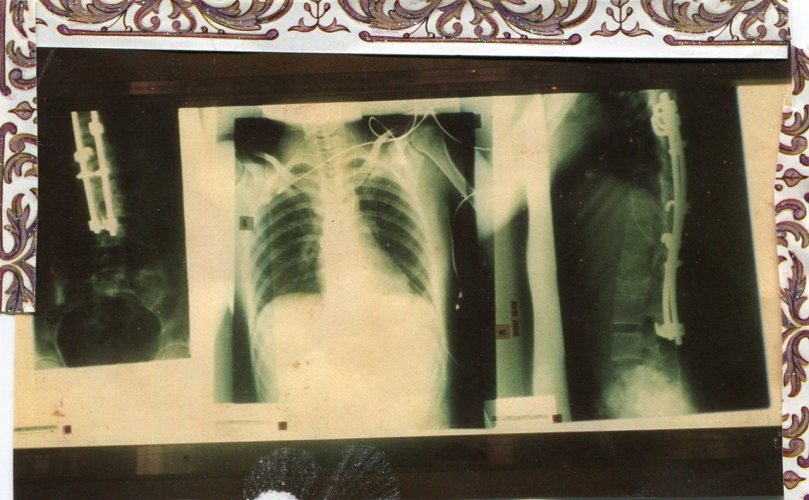

When I was in Primary school, the Government funded a scoliosis screening program, to pick up worrying curvatures early in a child’s life. At the time, I passed the screening with flying colours. Then, I broke my back. A few years later, after numerous surgeries, I was informed that my hip graft had failed, and I had scoliosis to such an extent that my heart, lungs and stomach were being crushed. Without major surgery, I would die. I was seventeen when I went into hospital to have this surgery. I had previously spent two years in a body brace, which unfortunately couldn’t save my spine, as the problem stemmed from the grafts failing. They at first opened my chest, somebody holding my heart whilst ribs were removed for grafting and put in via the front. Then I was turned over, and they operated on my spine, installing Harrington rods, screwed into place. I was later put in a fibreglass body cast.

Body cast at 17 years.